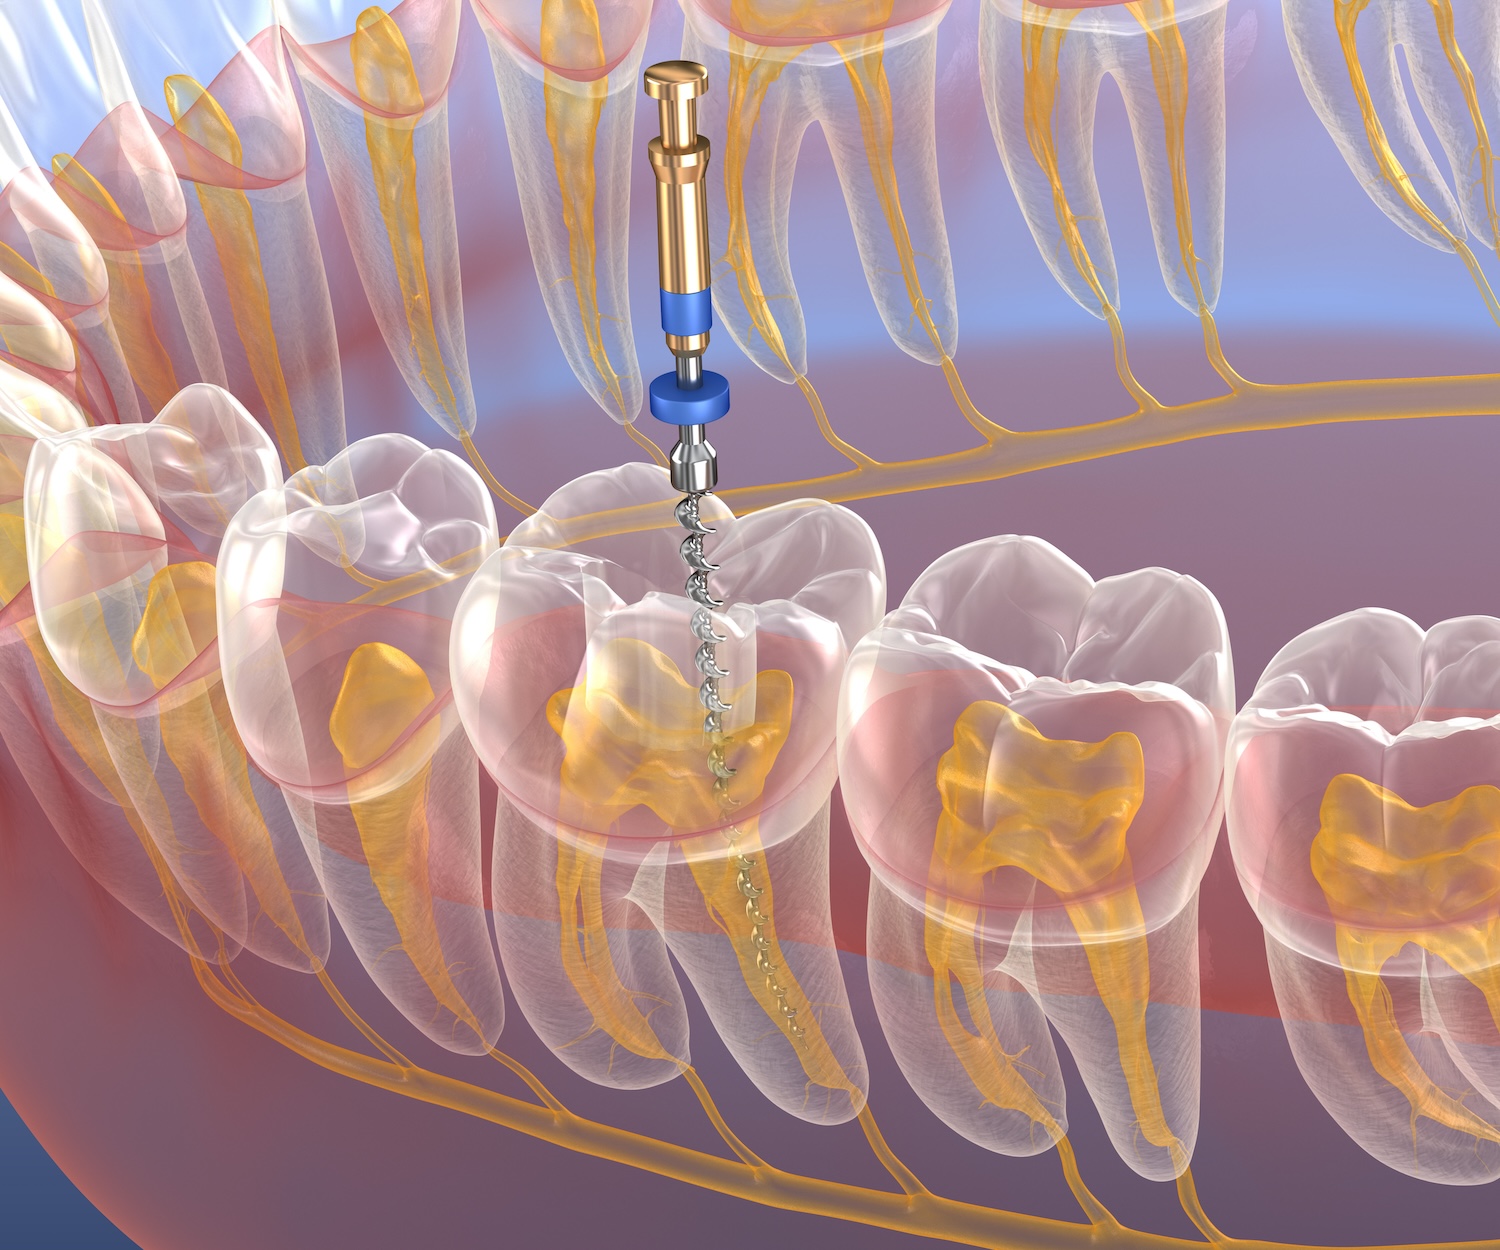

根管治療とは、むし歯や感染が歯の神経(歯髄)まで進行した場合に、歯を残すために行う治療です。歯の内部(根管)にある感染した神経や細菌を徹底的に除去し、薬剤で密封することで、炎症の再発を防ぎます。

この治療が成功すれば、抜歯せずに歯を残すことが可能になります。しかし、根管の構造は複雑で、非常に精密な処置が求められるため、治療の成功率には技術や設備の違いが大きく影響します。

根管治療は、一般的なむし歯治療に比べて非常に高度な技術を必要とします。その理由は、肉眼では見えないほど微細で複雑な根管内を、徹底的に清掃・消毒する必要があるからです。

根管の構造が複雑

根管の構造

歯の根の内部にある根管は、一本の太い管ではなく、非常に細かく枝分かれし、曲がりくねった形状をしています。その複雑さは人それぞれ異なり、まるで樹木の根のように複雑に入り組んでいます。肉眼でこの細部を正確に確認することは不可能で、感染した部分を完全に見つけるには、CTマイクロスコープといった精密な機器が不可欠です。